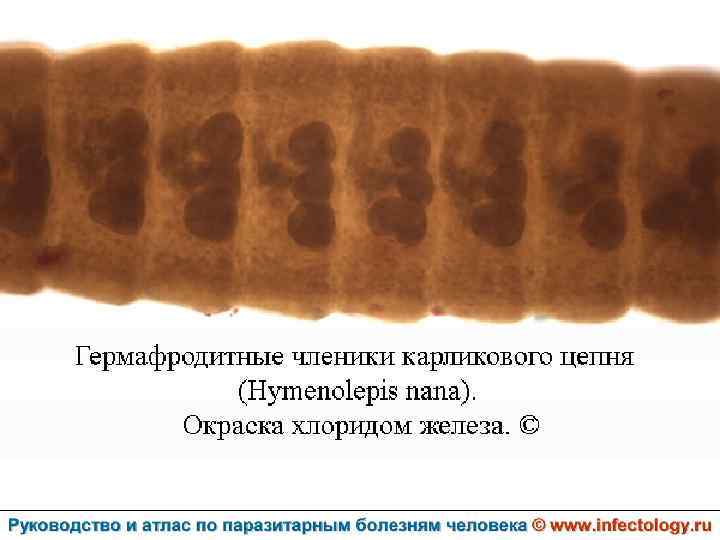

Гименолепидоз (шифр по МКБ 10 – B 71. 0) – контагиозный гельминтоз человека и некоторых мышевидных грызунов, характеризующийся, главным образом, нарушениями функций пищеварительного тракта.